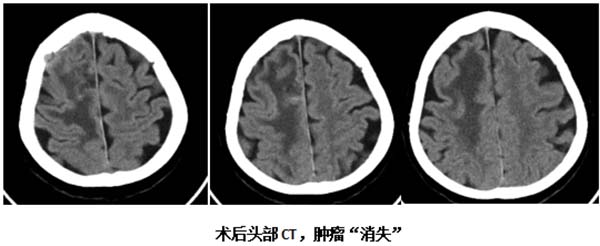

术后,患者在SICU接受了24小时专业监护,平稳度过危险期。康复速度令人惊喜:术后第二天症状明显缓解,第三天即可下地活动,左下肢肌力恢复正常。

病理科的精准诊断至关重要,术后病理回报为"大细胞神经内分泌癌"。根据这一结果,神经外科团队立即与肿瘤科衔接,实现从手术治疗到综合治疗的无缝对接。